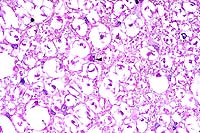

40x

obj.

- Case 22-1. Lung. Alveoli are filled with neutrophils

and lined by type II pneumocytes which occasionally contain eosinophilic

intranuclear inclusions bodies.